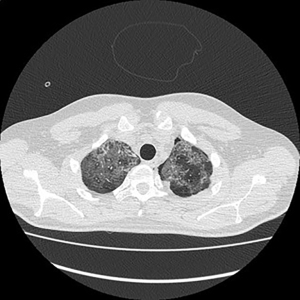

Electronic patient dataset provided checking anamnestic information. All records of the patients included were evaluated with the Hungarian patient-specific (Health Insurance Number coded) electronic database. The analysis was secured by full anonymization protocol. As far as the CT images are concerned, tissue free areas within the pleural space and mediastinal and/or pericardial collection with free air density have been graded. Bullae, pneumokele, fluid-free lung cysts less than 10% of the relevant lobe were categorised as stage I, destroyed lung, covering >50% of the ipsilateral hemithorax were categorised as stage III underlying destructive lung pathology. All positive cases between stages I and III were considered as stage II destructions. PTX less than 20% of ipsilateral lung surface was Grade 1 (Figure 1), while total PTX and those subtotal ones causing tension PTX were categorised as Grade 3. Any extension of free air collection between Grade 1 and 3 was categorised as Grade 2. The PM group was treated as a separate entity (Figure 2). Iatrogenic PTX was excluded from the study.